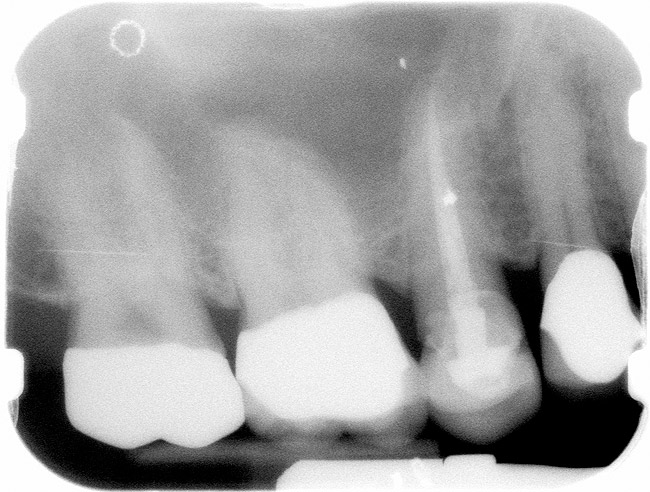

Case 1

A Class IN maxillary bicuspid was previously restored with a fiber post and an all-porcelain crown (Figure 1). The forces of the oral environment resulted in fracture of the fiber post and crown failure. The remaining fiber post in the root was removed, and anti-rotational areas were prepared for a cast post (Figure 2). A gold cast post was constructed at a dental laboratory, using an indirect technique (Figure 3). A porcelain-fused-to-metal (PFM) crown was constructed with a bevel finish to provide a ferrule and reduce forces on the post (Figure 4 and Figure 5).

Figure 1  X-ray of an endodontically treated second bicuspid restored with a fiber post, core, and all-porcelain crown.

Figure 1

Figure 2  Same second bicuspid as Figure 1 after removal of the fractured fiber post.

Figure 2